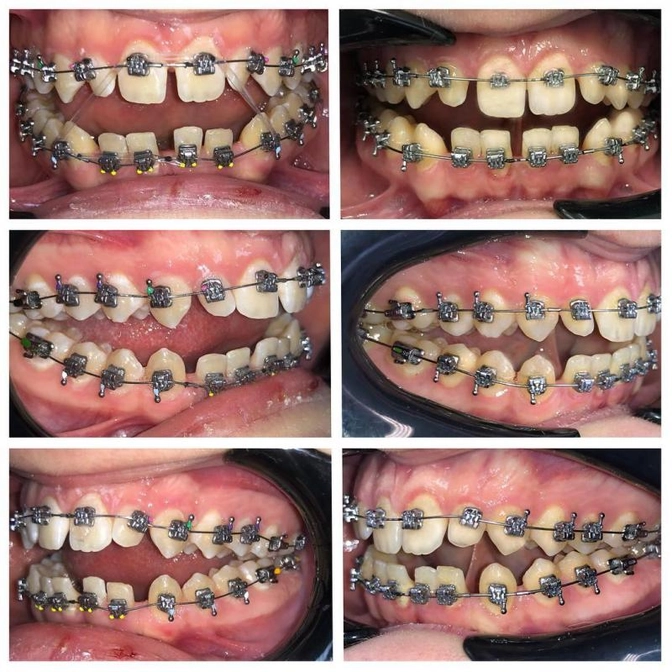

Лечение открытого прикуса на брекет-системе.

Лечение открытого прикуса в динамике за 1,5 месяца - отличная работа!

Случай непростой, еще много предстоит сделать впереди, но 17-летний пациент ооочень исполнителен и жаждет красивой улыбки.